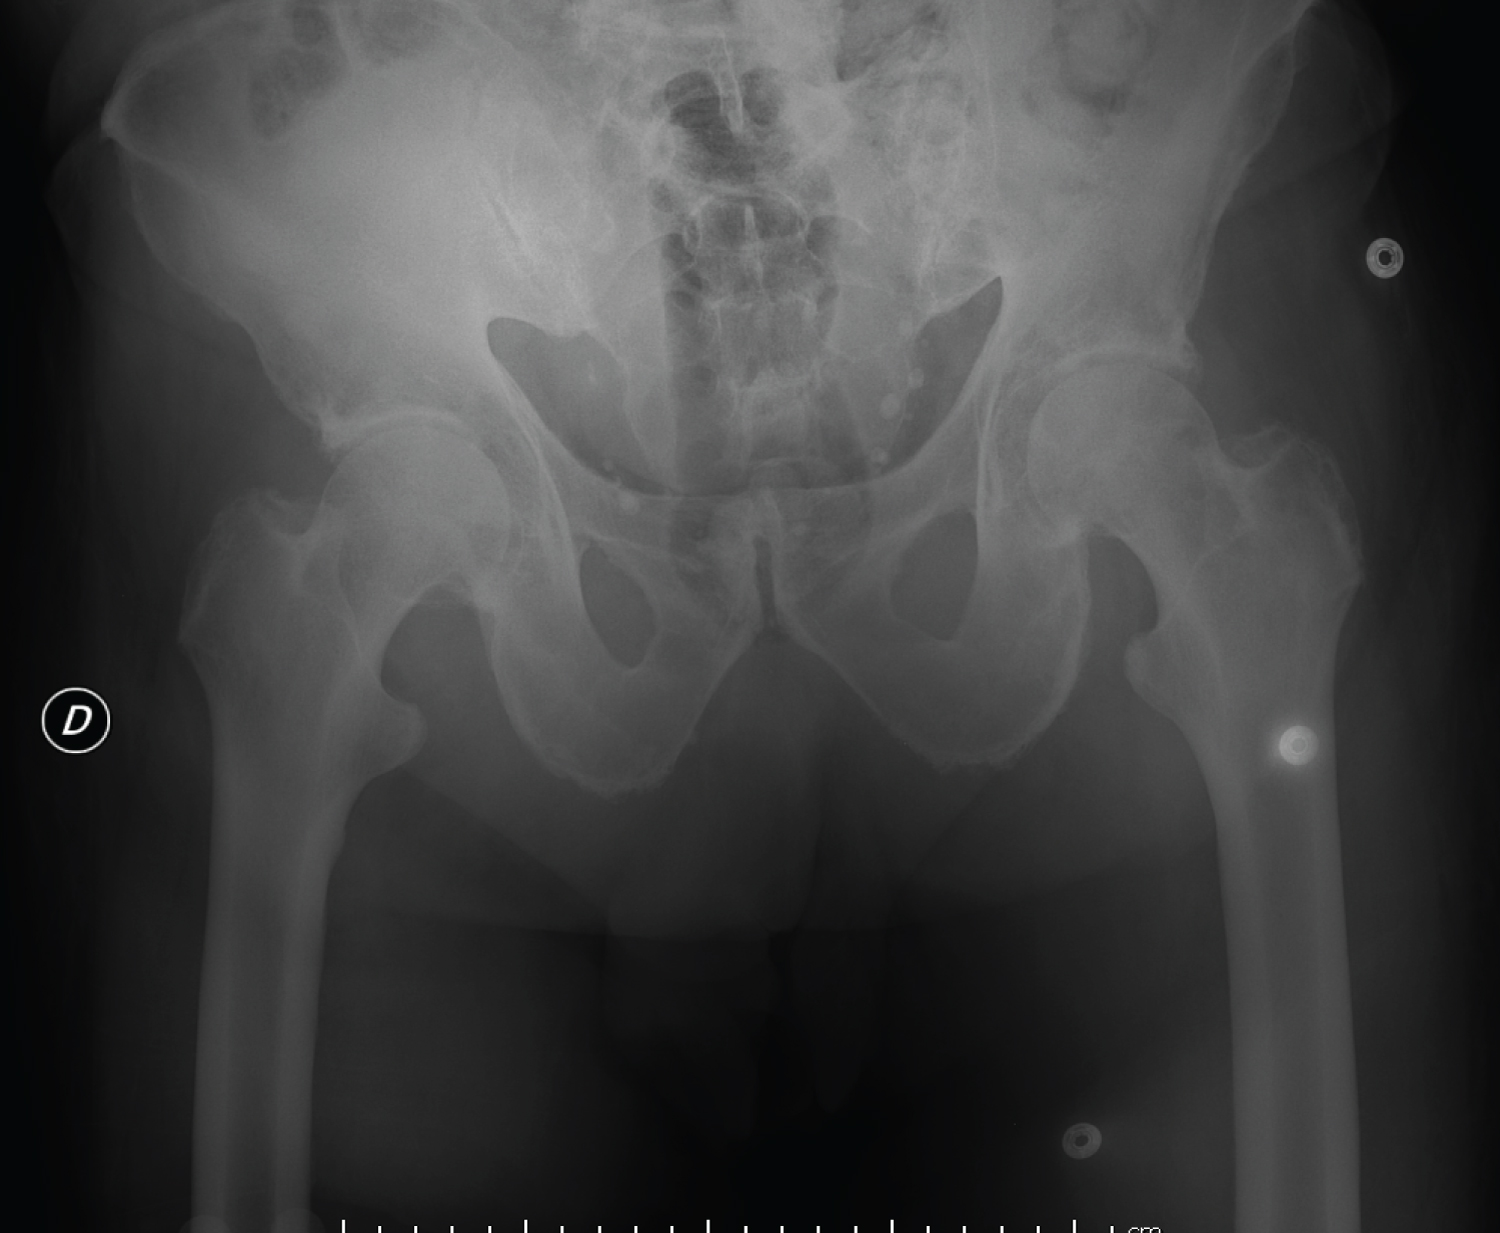

Reduction by external maneuver of the two dislocations was performed under sedation. Radiographic control confirmed the reduction (Figure 3). Immobilization with a Zimmer splint on both sides was applied for 3 weeks. Followed by gradual weight-bearing for another six weeks. 6 months after the accident, both hips remained stable with no signs of head necrosis (Figure 4).

Figure 4: Control X-ray after 6 months follow-up. View Figure 4